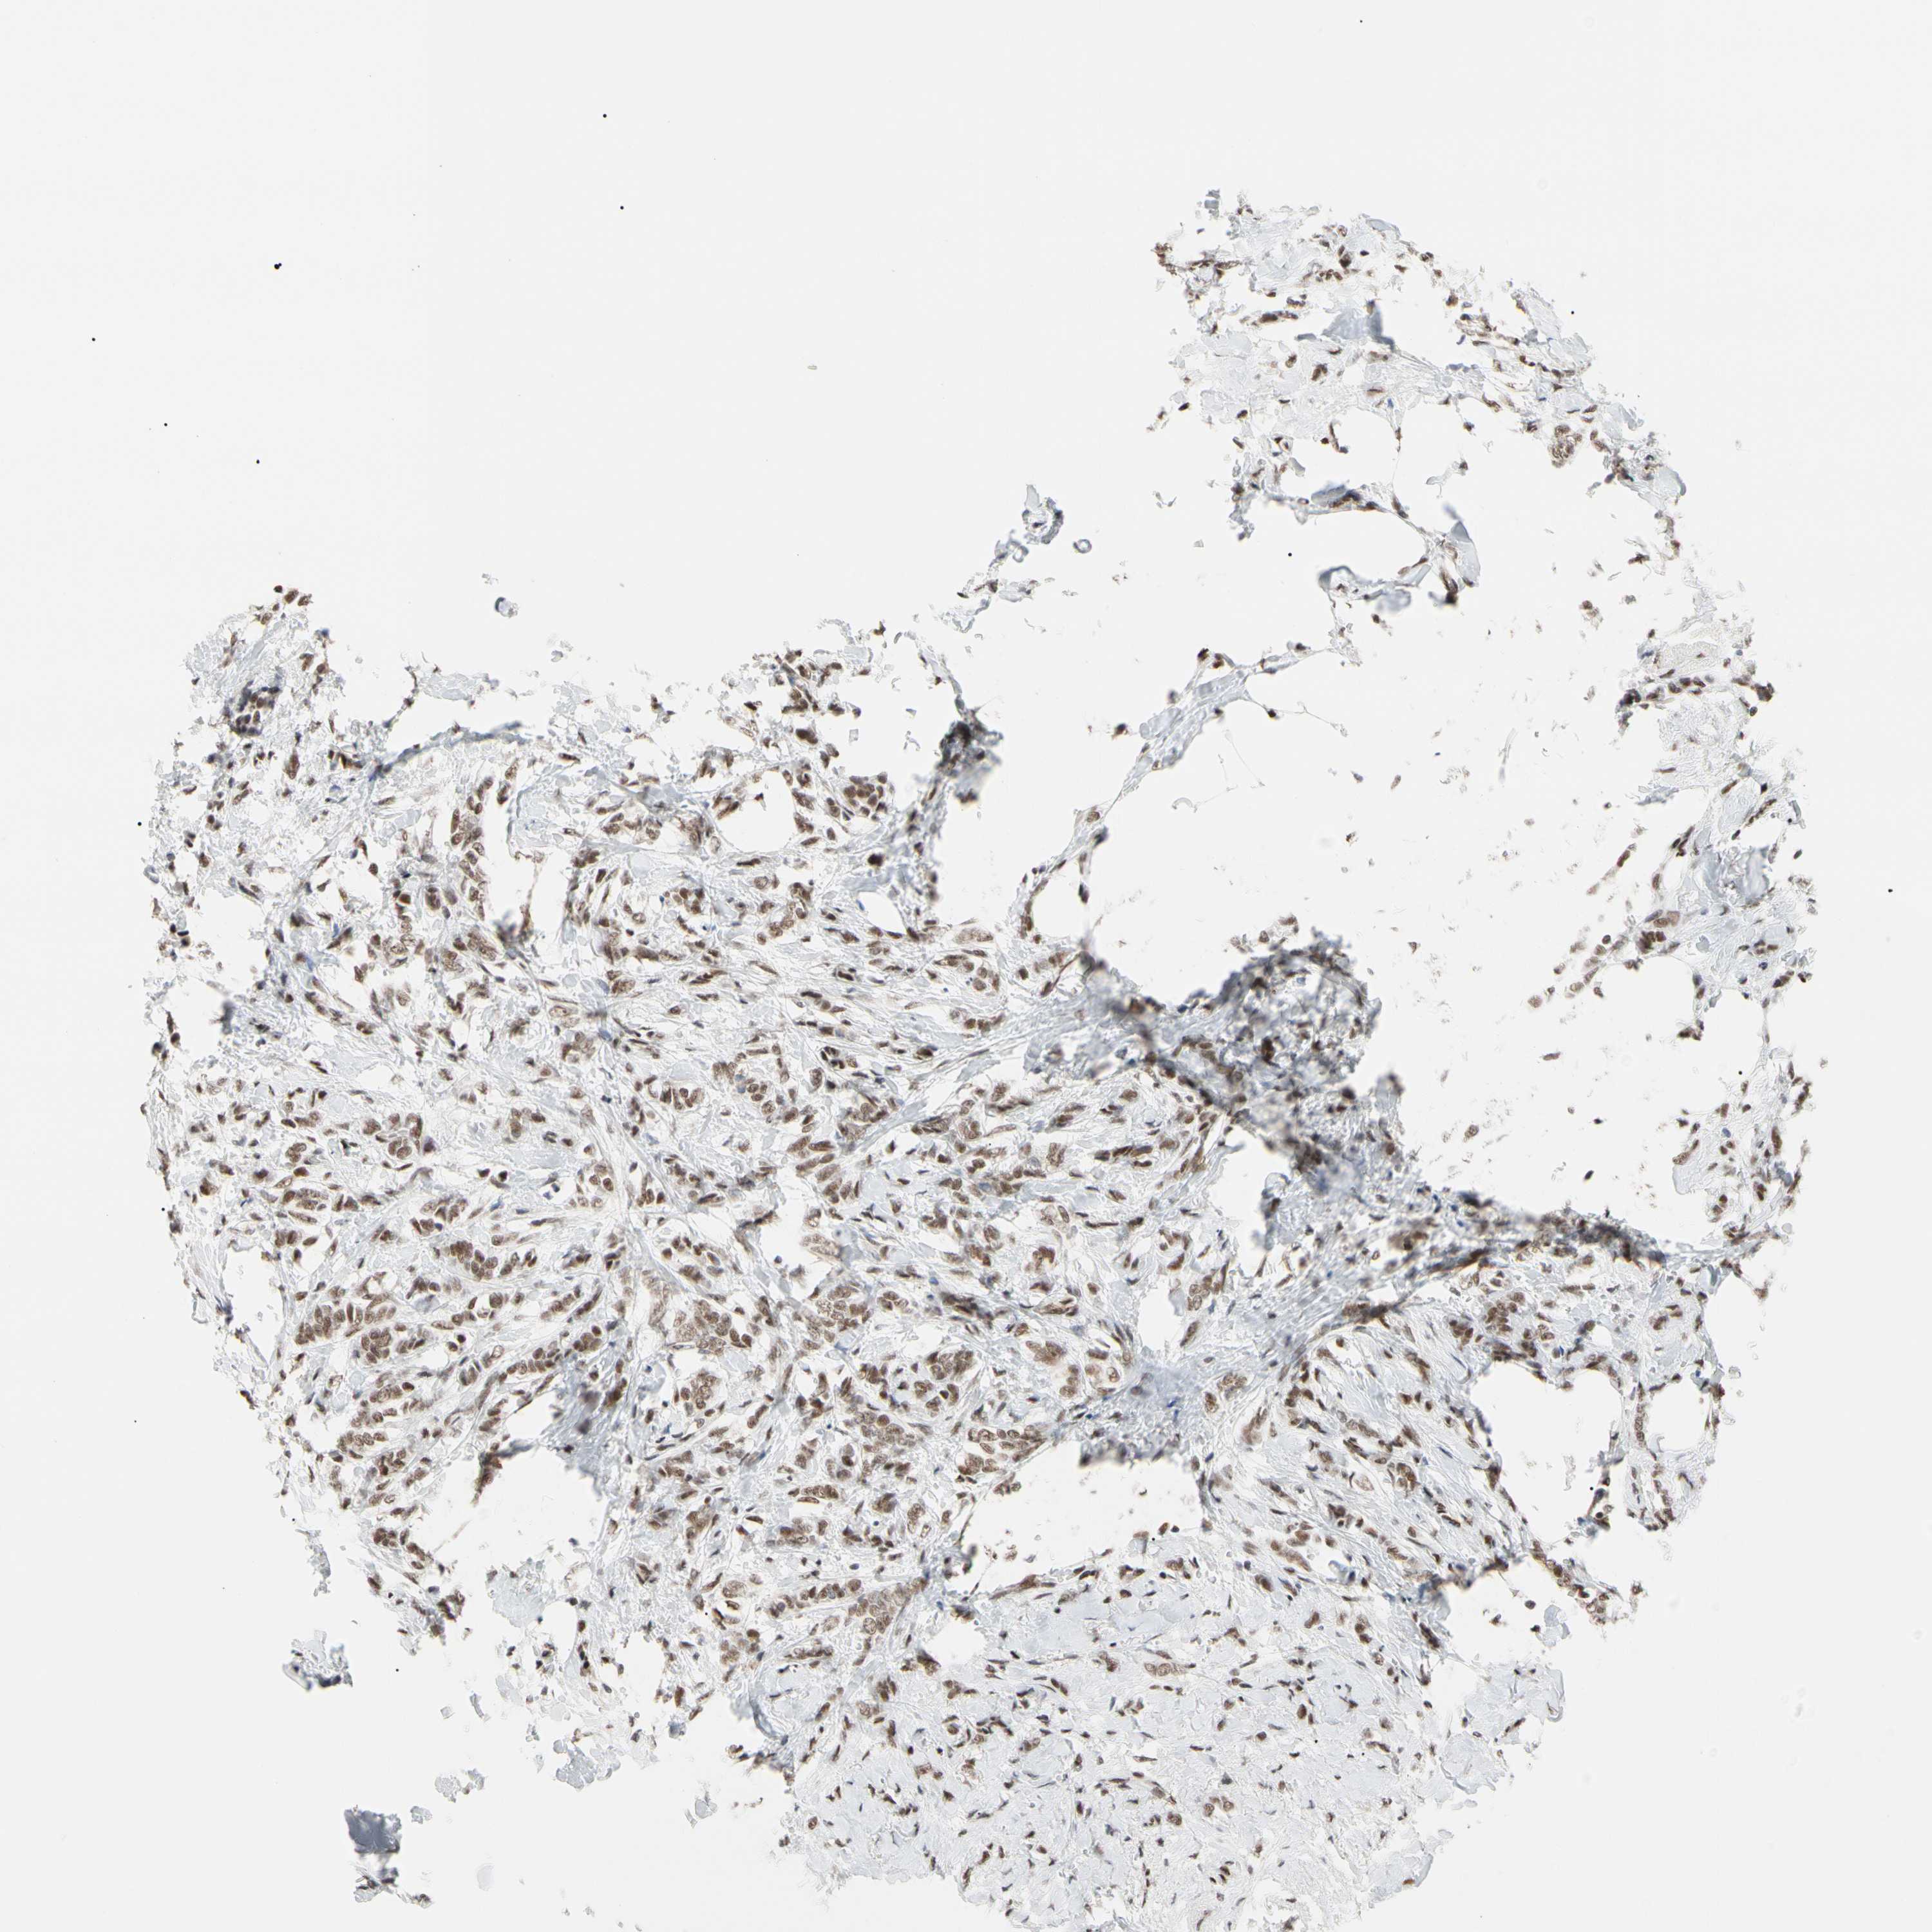

BRCA TCGA BRCA VALIDATION PROTEIN EXPRESSION

ANTIBODIES

AND

VALIDATION